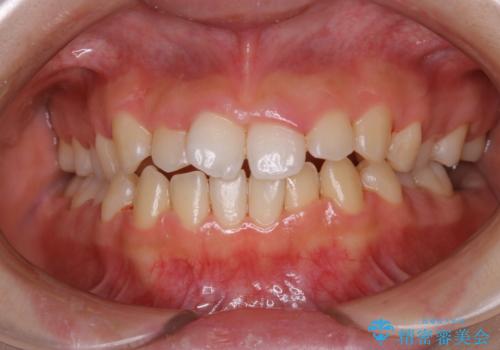

染め出しをしてのブラッシング指導とPMTCを行いました。

口腔内にはたくさんの細菌がいるため、ヌルヌルとしたプラーク(歯垢)が自然に歯の表面に付きます。

このプラーク(歯垢)にはたくさんの細菌が潜んでおり、虫歯や歯周病・口臭などの最大の原因です。そのため、毎日の歯磨きでプラーク(歯垢)をキレイに取り除くことが、健康な歯を保つためには欠かせません。